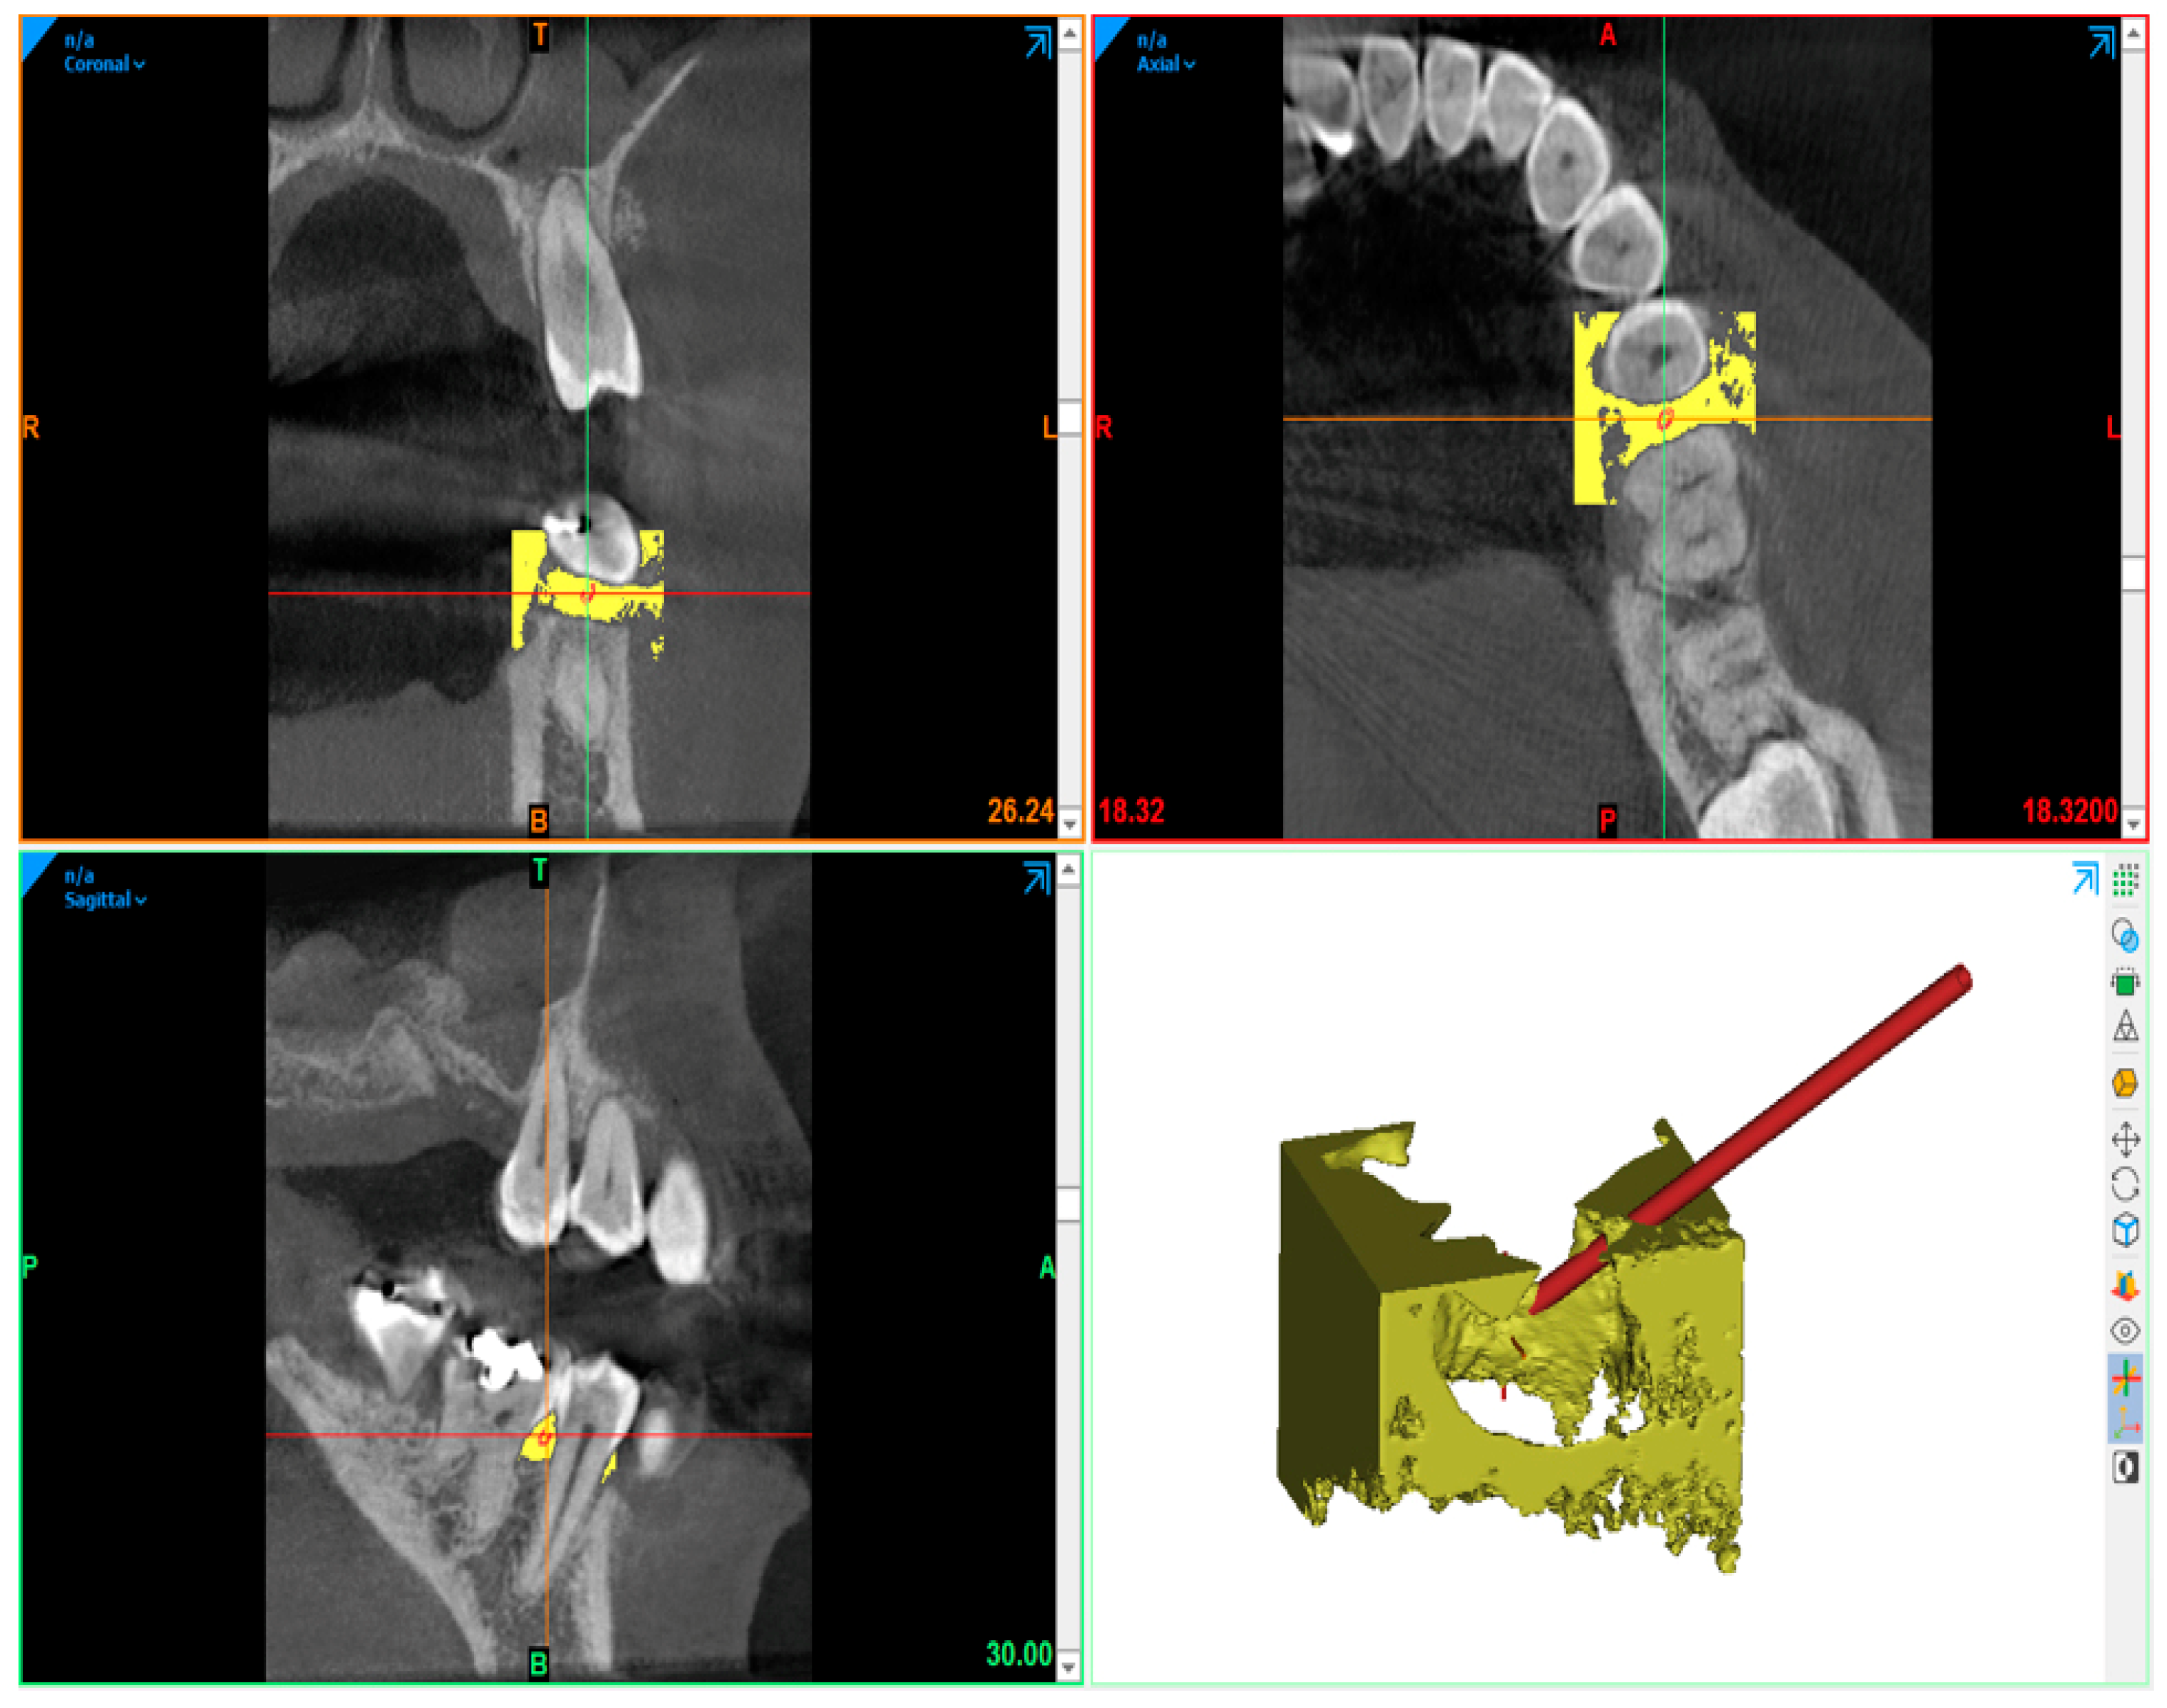

- Burgess, J. Digital DICOM in Dentistry. Open Dent. J. 2015, 9, 330–336. [Google Scholar] [CrossRef] [PubMed]

- Mohan, R.; Singh, A.; Gundappa, M. Three-dimensional imaging in periodontal diagnosis—Utilization of cone beam computed tomography. J. Indian Soc. Periodontol. 2011, 15, 11–17. [Google Scholar] [PubMed]